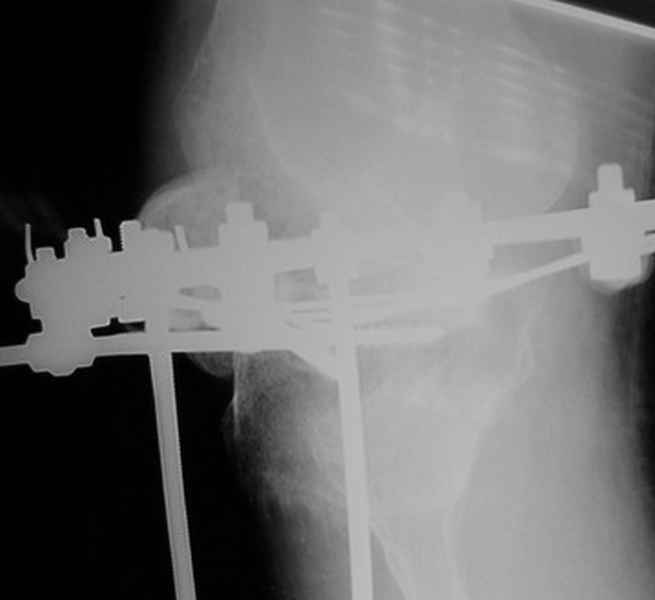

Пациент В. 53 лет, травма в феврале 2009. ДЗ. Открытый оскольчатый перелом нижней трети голени. При боли поступлении выполено ПХО, аппарат Илизарова. В последующем проводили ВХО, резекция костных отломков, укорочение 6 см, рана зажила. Была выполнена остеотомия большеберцовой кости в проксимальном отделе, резекция. Производилось тракция. На последних рентгенограммах выявлено, что одновременно с "выращиванием" регенерата произошло низведение надколенника на длину выращенного регенерата. Клинически: активное разгибание сохранено, объем движений в колене 180-110 градусов. Черными стрелками обозначен верхний край надколенника с одной и с другой стороны. Красная стрелка обозначает пальпируемую связку надколенника. Причина - остеотомия выше места прикрепления связки надколенника. Вопрос: была ли у кого подобная ситуация? Что делать? При первом обдумывании приходит решение: отсечение места прикрепления связки надколенника с костным блоком, перемещение на "правильное" место, укорочение сухожилия четырехглавой мышцы.

По снимкам - плотность регенерата хорошая, сложностей с фиксацией в него костного "основания" быть не должно.

К сожалению, подобное осложнение "нет-нет да и возникает" при удлинении, коррекции деформации голени. В англоязычной литературе оно описано как "patella baja". Один из вариантов лечения - проксимальное перемещение надколенника приемами чрескостного остеосинтеза.

По-моему, надколенник низвелся на величину, гораздо меньшую удлинению.

Я бы уменьшил диастаз между фрагментами сантиметра на два. Судя по снимкам, регенерат это может позволить.